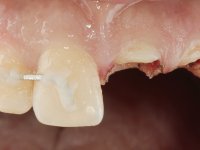

Paciente do sexo masculino, com 29 anos não fumador. Após atendimento hospitalar, na sequência de um traumatismo facial, surgiu na consulta com os dentes 2.1 e 2.2 com extensas fraturas coronais e com exposição pulpar. As fraturas eram justa-ósseas a nível palatino e as raízes apresentavam mobilidade acentuada. Os dentes 1.3,1.2 e 1.1 apresentavam-se ferulizados com um arame ortodôntico. A ferulização abrangia as superfícies vestibulares e palatinas. Os três dentes em conjunto também apresentavam mobilidade. O lábio inferior apresentava-se ainda suturado e a higiene oral era sofrível.

Foi feito o tratamento endodôntico dos dentes 2.1 e 2.2.de imediato, a sintomatologia que o paciente manifestava a isso impunha. Na mesma consulta foi realizada uma extensa gengivetomia com o bisturi elétrico, no sentido de expor os limites cervicais da fratura. Foram colocadas resinas compostas nos remanescentes radiculares com a intenção de reformular a emergência dos tecidos moles. Realizei a impressão dos remanescentes radiculares para confeção em laboratório de uma ponte provisória. A ponte provisória de 2 elementos, apresentava um formato que visava no futuro acomodar o coto dos espigões falsos cotos que iria ser cimentados nos remanescentes radiculares. Apresentava um reforço metálico palatino e dois apoios para os dentes adjacentes, um mesial e outro distal. Os remanescentes radiculares foram preparados para a confeção de dois espigões falso coto fundidos. As linhas de acabamento cervical foram definidas e os canais radiculares desobturados e preparados. A impressão foi realizada com a utilização de tutores de plástico com a técnica de dupla mistura. O afastamento gengival foi feito utilizando pasta de caolino. A ponte provisória foi rebasada em boca com acrílico auto polimerizavel, cimentada provisoriamente sobre as raízes e os apoios colados aos dentes adjacentes. No laboratório foram confecionados os E.F.C. fundidos, tendo o cuidado de preservar espaço para a definição no re preparo dentário da linha de acabamento cervical. Removida a ponte provisória foi feita a cimentação dos E.F.C. fundidos com cimento de ionómero de vidro reforçado com resina. A ponte provisória teve que ser retocada para permitir a acomodação dos cotos e simultaneamente foi readaptada à redefinida linha de acabamento cervical. Durante 2 meses a ponte provisória acompanhou a estabilização periodontal das raízes traumatizadas e simultaneamente conseguiu a maturação da arquitetura gengival.